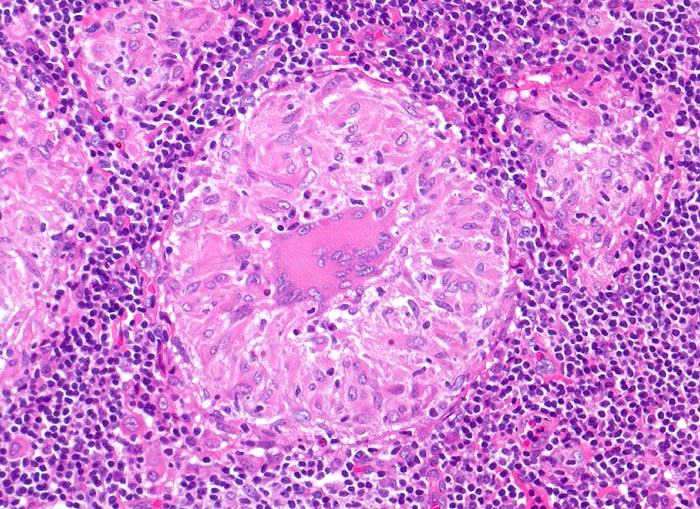

Sarkoidosegranulome bestehen aus Epitheloidzellen mit einem peripheren Lymphozytensaum. Mehrkernige Riesenzellen, meistens solche vom Langhans-Typ mit hufeisenförmig angeordneten Kernen und Asteroidkörperchen (> 4173) können zusätzlich vorhanden sein. Diese Granulome enthalten meist keine Nekroseherde (=produktives Granulom). Man findet diesen Granulomtyp hauptsächlich in Lymphknoten, aber auch in inneren Organen und in der Haut. Die Sarkoidosegranulome zeigen in späteren Stadien eine charakteristische perigranulomatöse und die Granulome septierend unterteilende Fibrose (> 4015).

• Wenig erhaltenes Lymphknotengewebe (blau).

• Konfluierende Granulome aus grossleibigen Epitheloidzellen.

• Wenige mehrkernige Riesenzellen.

• Kleinere Nekroseareale im Zentrum grösserer Granulome. (Die Nekrosen sind untypisch für die Sarkoidose, können aber bei grossen Granulomen gelegentlich vorkommen).

• Perigranulomatöse Fibrose. Das sollte der Kliniker dem Pathologen mitteilen: